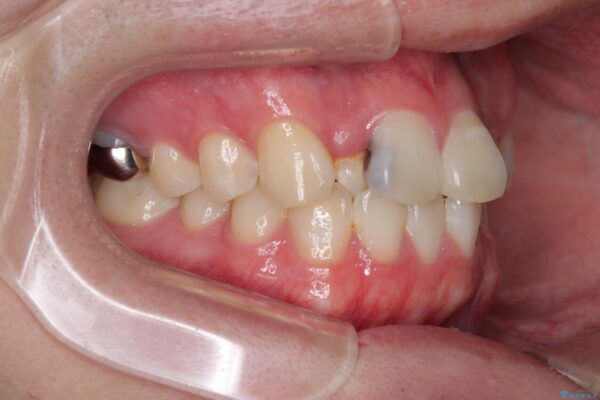

「歯並びがデコボコしていて、上下の中心がズレているのが気になる…」という悩みで来院された患者さまの症例をご紹介します。

初診時の状態

・上下ともに歯がきれいに並びきらず、がたつきが見られました。

・上下の前歯の中心(正中)がずれています。

・特に上顎の幅が狭いため、下顎の歯列も内側に入り込み、歯が並ぶスペースが不足していました。

治療前

• 1年でここまで変わる!歯列のがたつきと正中のズレを改善した矯正治療(メタルブラケット×MARPE) 治療前画像